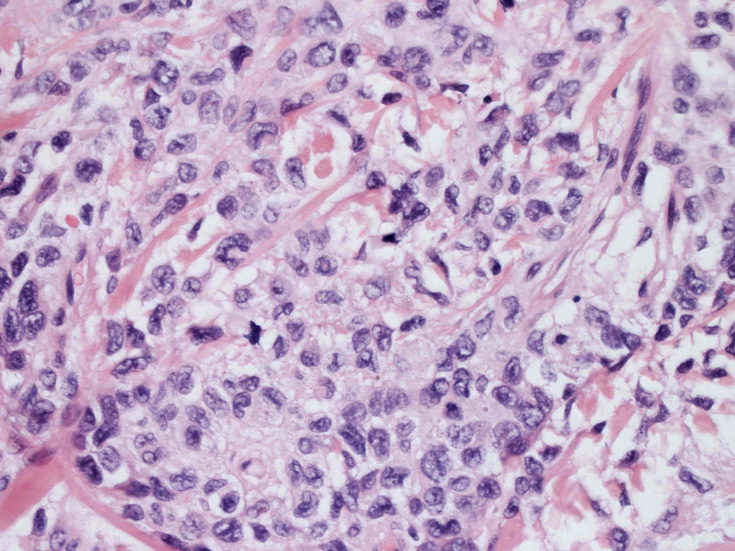

大型細胞の増殖よりなる腫瘍。縦溝,しわ,切れ込みのある核をもった大型細胞も出現する。クロマチンは顆粒状で核小体も明瞭である。核分裂は >50/10hpfと多い。eosinophilsは少ない。壊死が多発することがある。未分化ないし低分化な細胞像, 組織所見のため鑑別診断は多岐にわたり、的確な免疫染色を行う必要がある。

皮膚に異型細胞の浸潤がみられる。異型細胞は表皮内に浸潤するほか、表皮真皮境界部, 真皮, 皮下脂肪組織にもびまん, 結節様の浸潤所見を示す。血管周囲に浸潤、集蔟する所見も多く見られる。 増殖浸潤細胞の核には類円形や腎臓形, またはへこみ, 切れ込み, 溝などを有する多型な核が認められる。クロマチンは粗でvesicularな核が多い。核小体の明らかな核もある。好エオジン性の核内封入体様構造も少数に見られた。mitosisは容易に認められる。hyperchromaticな多型核, bizzarreな細胞が高頻度に認められ異型度は高いと考えられる。細胞質は境界不明瞭, 淡明または泡沫様の 好エオジン性胞体である。